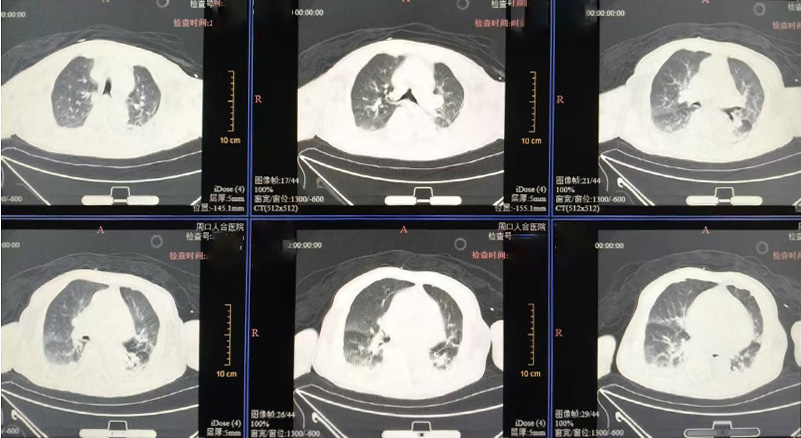

入院时患者已昏迷,生命体征极不稳定:血压显著偏低(休克状态),血氧明显下降,心率严重迟缓。检查提示:血钾显著升高(已达心脏骤停风险)、严重代谢性酸中毒、肾功能严重衰竭,感染及心功能指标严重异常。明确诊断为:尿毒症脑病、感染性休克、多脏器功能衰竭,病情危重至极,随时可能呼吸心跳骤停。

我院立即启动多学科会诊,重症医学科、肾内科、呼吸科、心内科、感染科等专家迅速集结。团队第一时间给予气管插管、呼吸机辅助通气、中心静脉置管、纤支镜吸痰、强效抗感染,并紧急启动床旁CRRT(连续性肾脏替代治疗),24小时清除血液毒素、纠正高钾血症和酸中毒,同时输血维持生命体征。

经过10天全力救治,患者病情显著好转:感染有效控制,心功能指标大幅下降;神志清醒,呼吸血压平稳,成功拔除气管插管、停用升压药;内环境逐步代偿,肾功能及电解质紊乱逐步纠正。患者已转入普通病房继续康复。